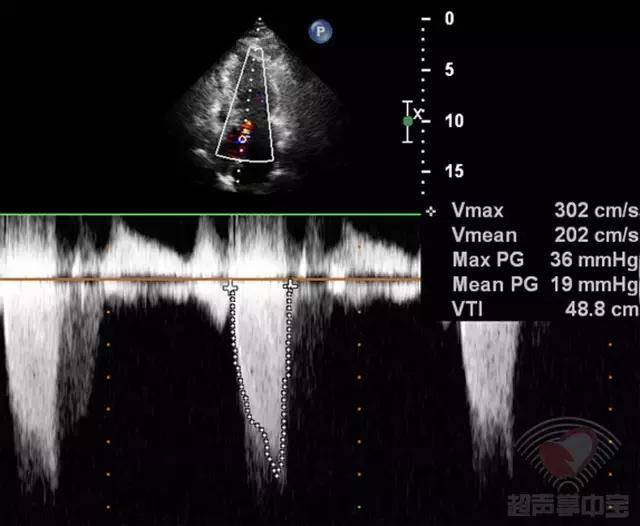

心尖五腔心切面CDFI:左室流出道呈五彩镶嵌花色血流信号。CW:左室流出道最大瞬时流速和压差增大(Vmax:302cm/s,PG:36mmHg),频谱峰值后移(图2)。

图2非对称性肥厚型梗阻性心肌病:心尖五腔心切面CW测左室流出道峰值流速302cm/s